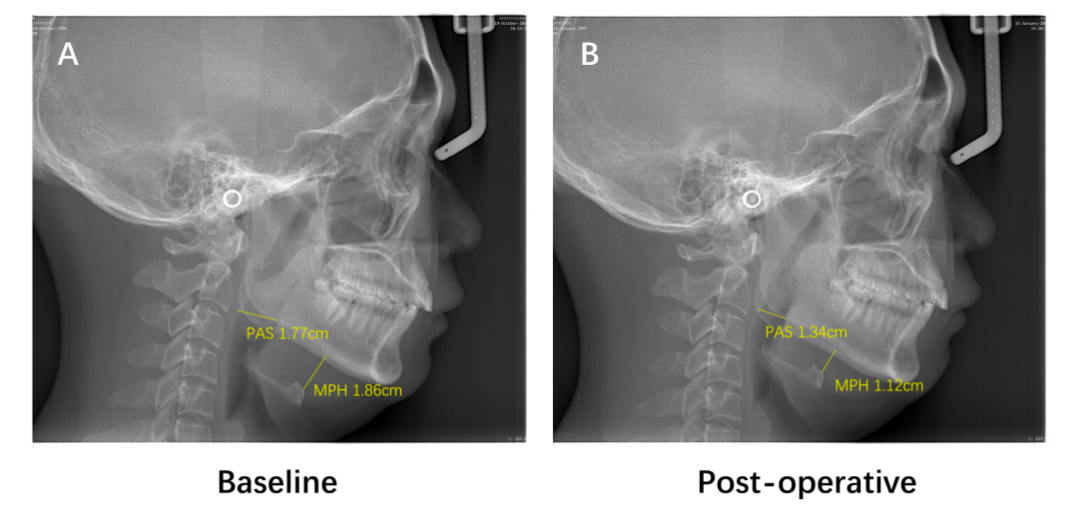

耳鼻咽喉科团队采用国际现主流的药物诱导睡眠内镜(DISE,简称睡眠内镜)检查,精准定位患者入睡时上气道堵塞部位,结合保留悬雍垂、悬吊前移软腭的改良UPPP手术,及微创的舌打孔射频消融技术,解除软腭和舌根两大阻塞平面。采用精准诊断技术,团队严格筛选了适合手术治疗的患者,为他们实施了改良UPPP手术和微创的舌打孔低温等离子消融技术,在减轻患者术后疼痛的同时,更实现术后无需带管入住ICU,显著降低患者痛苦及手术风险,加速患者康复。随访2年以上的结果提示呼吸暂停低通气指数(AHI,客观反映呼吸受阻次数)平均下降58.8%,2/3患者长期有效。

术前术后头颅侧位片提示患者舌体缩小、舌骨上提,上气道解剖异常得以解除